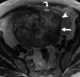

Benign ovarian fibroma

The ovarian fibroma, also fibroma, is a benign sex cord-stromal tumour. Ovarian fibromas represent 4% of all ovarian neoplasms. [Source: Wikipedia ]